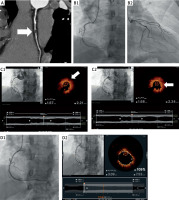

Figure 1

A – computed angiography tomography of the right coronary artery (RCA) (arrow: coronary artery calcification (CAC)). B1 – coronary angiography of RCA, before percutaneous coronary intervention (PCI) (arrow: CAC). B2 – coronary angiography of the left coronary artery (LCA), before PCI. C1 – optical coherence tomography of RCA, before PCI (arrow: lipid core). C2 – optical coherence tomography of RCA, before PCI, arrow: site of rupture). D1 – angiographic image of RCA, just after PCI. D2 – optical coherence tomography of RCA, just after PCI

A 48-year-old patient with dyslipidemia and hypertension, with a history of non-ST-elevation myocardial infarction (NSTEMI) treated with percutaneous coronary angioplasty of the marginal branch, and radiotherapy for non-Hodgkin’s lymphoma, was admitted for CCTA. The exertional test, performed a month before admission, was electrocardiographically positive. CCTA, assessed jointly by a radiologist and a cardiologist, revealed severe stenosis in the right coronary artery (RCA) with a high-risk lipidic plaque (Figure 1 A).

The patient was scheduled for urgent coronary angiography and admitted on the next day. While being transported to the catheterization laboratory on foot, the patient reported chest pain. The electrocardiography (ECG) performed in the catheterization laboratory showed ST segment elevation in leads II, III, and aVF. Coronary angiography revealed a critical stenosis of 99% in the middle segment of the RCA (Figure 1 B1) and only minor plaques in the left coronary artery (LCA) (Figure 1 B2). Optical coherence tomography (OCT) confirmed the presence of thin-cap fibroatheroma with lipid core (Figure 1 C1) and ruptured atherosclerotic plaque with a thrombus (Figure 1 C2), and the patient was deemed eligible for immediate coronary angioplasty. Drug-eluting stent implantation (Ultimaster 2.75 × 44 mm, 20 atm) was performed under optical coherence tomography (OCT) guidance.

The result of the procedure was optimal (Figure 1 D1). It was confirmed in OCT, which showed a minimal stent area of 5.5 mm2 and good apposition of the stent (Figure 1 D2). A day later, the patient was discharged home in good condition.